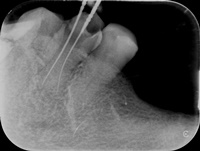

Pacjentka zgłosiła się z bólem. Kilka miesięcy wcześniej leczona kanałowo lewa dolna szóstka. Ząb wrażliwy na nagryzanie. Podjęto decyzję o ponownym przeleczeniu kanałów korzeniowych. Zamknięto perforację przy wejściu do dalszego kanału, usunięto złamaną igłę lentulo z dalszego kanału, udrożniono mezjalne kanały, aż do perforacji korzenia w policzkowym bliższym kanale. Wypełniono dalszy kanał gutaperką, bliższe kanały wypełniono MTA. Ząb do obserwacji, najprawdopodobniej będzie wykonana resekcja wierzchołków bliższego korzenia, na poziomie perforacji.

Reendo 46.